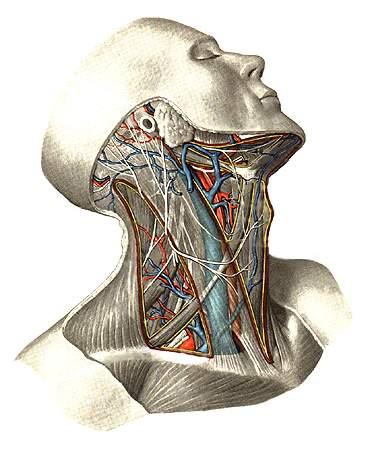

Виллизиев круг является ключевым элементом для нормального кровоснабжения всех систем нашего организма. Он образуется крупными позвоночными артериями, которые делятся на левую и правую ветви. В нормальных условиях развитие этих артерий происходит равномерно. Подключичная артерия, направляясь к черепной полости, разветвляется на входе.

Серьёзные изменения затрагивают область костного канала и артерии, которая в него впадает. При гипоплазии ткани головного мозга получают значительно меньше крови, что может привести к негативным последствиям.

УЗИ сосудов головы и шеи. Основное внимание уделяется дуплексному ангиосканированию, которое позволяет получить изображение артерии и оценить характеристики кровотока, включая его интенсивность, тип и диаметр. Этот метод безопасен и не представляет угрозы для здоровья пациента.

Томография шейной и головной области с контрастным усилением. Исследование проводится с использованием магнитно-резонансных и компьютерных томографов, при этом сосуды заполняются контрастными веществами для более детального анализа.

Ангиография. Этот метод позволяет графически зафиксировать особенности расположения, анатомическую структуру и соединения сосудистых образований. С помощью рентгеновского оборудования можно оценить состояние позвоночной артерии, заполнив её контрастным веществом. Изображение выводится на экран, а для введения контраста производится пункция крупной артерии на одной из конечностей.